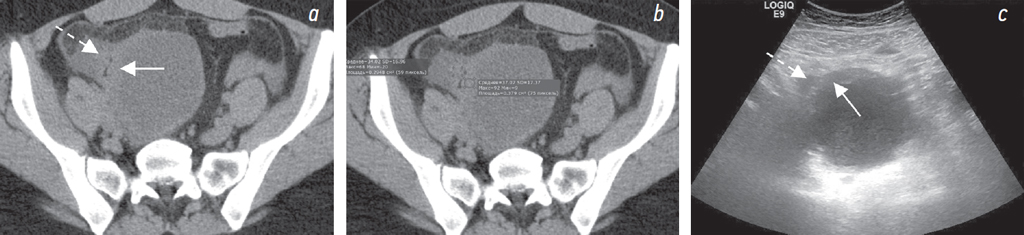

При КТ без внутривенного контрастирования выявлены свободная жидкость в полости таза, по боковым фланкам, около печени (рис. 1, а, c, d); в области правого яичника образование жидкостной плотности размерами до 77 × 67 мм (рис. 2, а), стенка неравномерной толщины, до 7 мм (рис. 3, а, b); инфильтрация большого сальника (рис. 1, f), остальные органы без особенностей. Заключение: КТ-признаки свободной жидкости в брюшной полости, образования правого яичника. При КТ грудной клетки не выявлены признаки неопластического или инфекционного процесса.

Рис. 1. На нативной КТ-томограмме в аксиальной плоскости (а) и на трансабдоминальной сонограмме (b) визуализируется свободная жидкость около печени (стрелка). На нативных КТ-томограммах в сагиттальной (c, d) плоскости и на трансвагинальной сонограмме (e) показана кровь в виде свободной жидкости в маточно-пузырном пространстве (круг) и в маточно-прямокишечном пространстве (звездочка). Эндометриоидная киста (молния) визуализируется на КТ-томограммах (c, d), трасвагинальной сонограмме (e). На КТ-томограмме (d) показаны коэффициенты ослабления рентгеновского излучения в единицах Хаунсфилда в эндометриоидной кисте и в свободной жидкости в полости малого таза. Инфильтрация большого сальника справа (пунктирная стрелка) на КТ-томограмме во фронтальной плоскости (f)

При УЗИ: свободная жидкость в брюшной полости (преимущественно около печени, в гепаторенальном кармане, в правом боковом канале толщиной слоя до 10 мм) и малом тазу (рис. 1, b, e). В области правых придатков определяется образование (размерами около 65 × 70 × 90 мм) с содержимым в виде мелкодисперсной эховзвеси («матовое стекло»), стенками неравномерной толщиной 7–10 мм с прилежащими по наружному контуру гипоэхогенными массами (сгустки?) (рис. 3, c). В околоматочном пространстве эховзвесь в жидкости идентична содержимому кисты в яичнике (рис. 4, а, b). Матка и левый яичник (рис. 2, b) без эхоструктурных особенностей. Паренхиматозные органы брюшной полости и забрюшинного пространства без УЗ-признаков структурной патологии. Заключение: УЗ-признаки могут соответствовать гемоперитонеуму вследствие разрыва кисты правого яичника (вероятно, эндометриоидной).